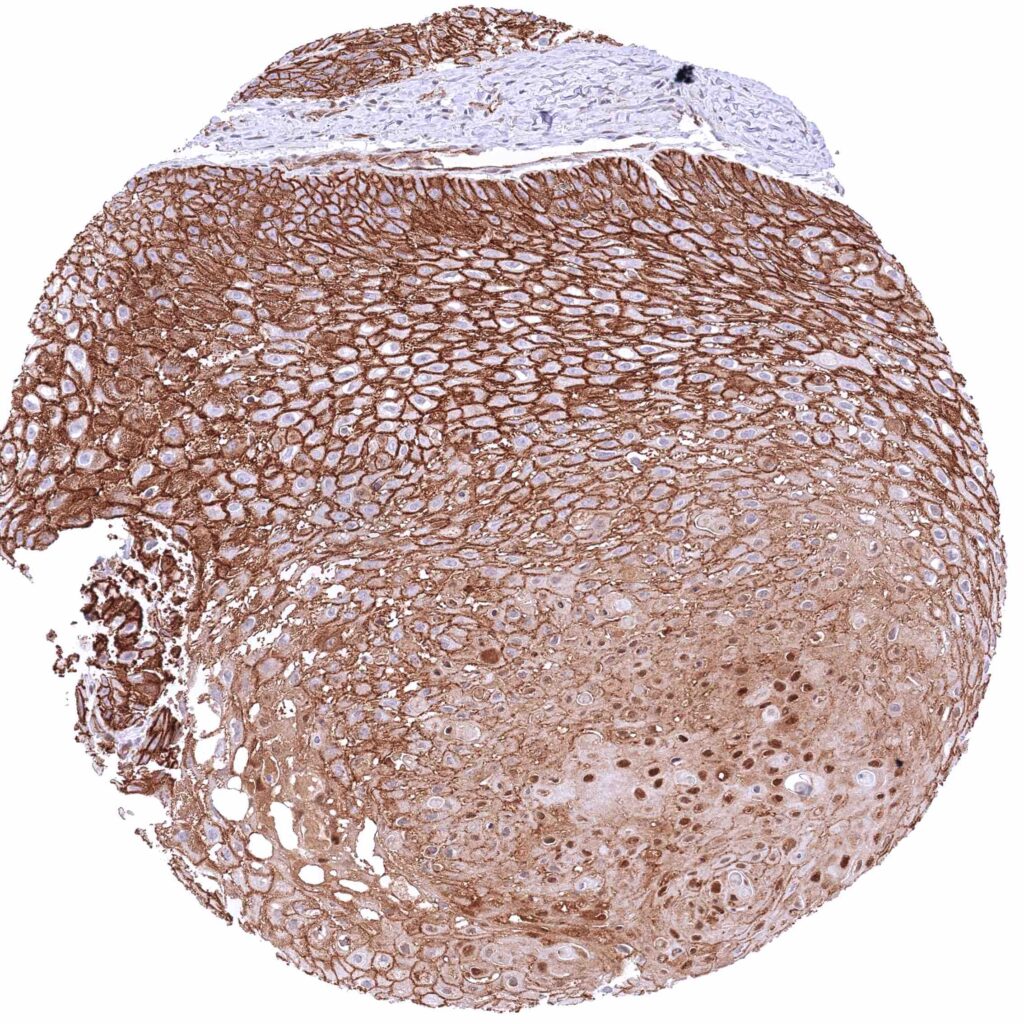

Uterus, cervix – Squamous cell carcinoma with strong membranous β-Catenin positivity of tumor cells.

Uterus, cervix – Squamous cell carcinoma with strong membranous β-Catenin staining of tumor cells. There might be an additional slight cytoplasmic staining in this case.